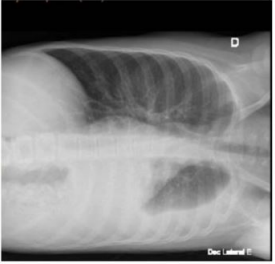

Paciente de 10 anos, feminino, previamente hígida, apresenta tosse e coriza há 7 dias e febre há 5 dias, prostração e dor abdominal há 2 dias. Nega trauma ou qualquer lesão ou infecção prévia ao quadro atual. Ao exame físico está em regular estado geral, pálida, com FC: 120 bpm, FR: 31 ipm, discreta tiragem de fúrcula sem outros sinais de desconforto respiratório. Ausculta cardíaca sem alterações, ausculta pulmonar com crepitações, diminuição de murmúrio vesicular e da ausculta da voz em base esquerda. Abdome flácido, levemente doloroso à palpação profunda. Oximetria de 95% em ar ambiente. Solicitado teste rápido para influenza A positivo. Hemograma e proteína C reativa (abaixo) e hemocultura (em andamento) e Raio X de tórax em pé e decúbito lateral esquerdo (abaixo).